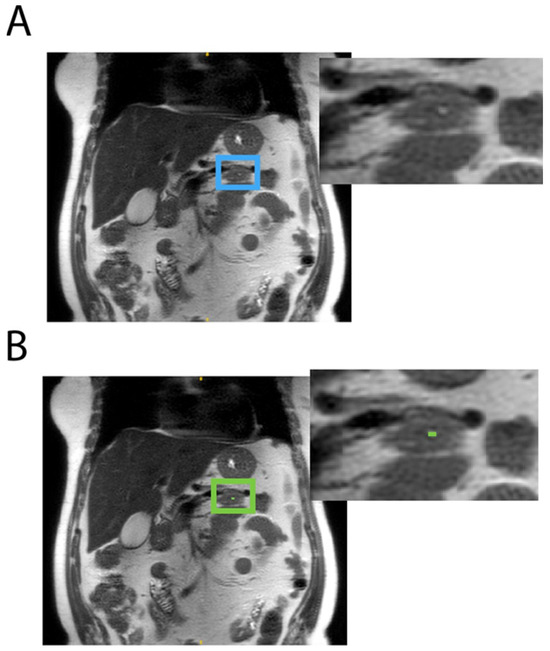

2.2. Annotations

2.3. Agreement Evaluation